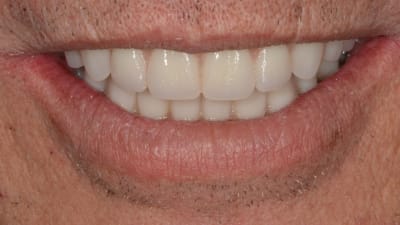

Case Reports Restorative Direct Restorative Minimally Invasive Dentistry: A Conservative Approach to Smile Makeover By Jeffrey M. Rosenberg, DDS January 01, 2017 14 min read